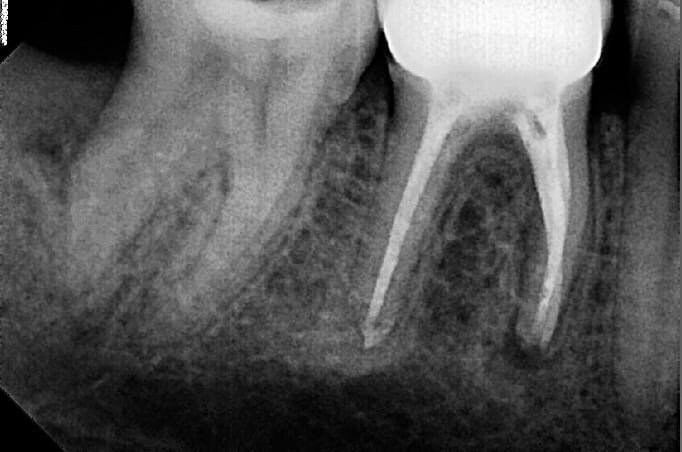

Всем привет. Я зубной техник и историю, которую сейчас расскажу, услышал от моего товарища стоматолога-хирурга. Случай из неотложки. Мой товарищ работает в областной стоматологической поликлинике и по неотложке оказывает помощь пациентам. И вот в одно из дежурств к нему приезжает пациент с сильной зубной болью и повышенной температурой. От себя скажу, что работа в неотложке - это тот еще стресс и напряжение, поскольку, во-первых пациентов бывает настолько много, что даже не продохнуть, а иной раз попадают настолько сложные пациенты, к которым нужно подходить очень основательно с заблаговременным планированием операции. Так вот, на оказание неотложной помощи к нему обратился пациент. Из жалоб были сильные боли зуба, которые длились порядка двух недель, но он не обращался за помощью, так как было некогда, да и стоматологов он ну очень уж боится. При осмотре пациента стоматолог-хирург заметил сильное воспаление и отек в шейном отделе. Достаточно широко рот открыть пациент не смог. И в